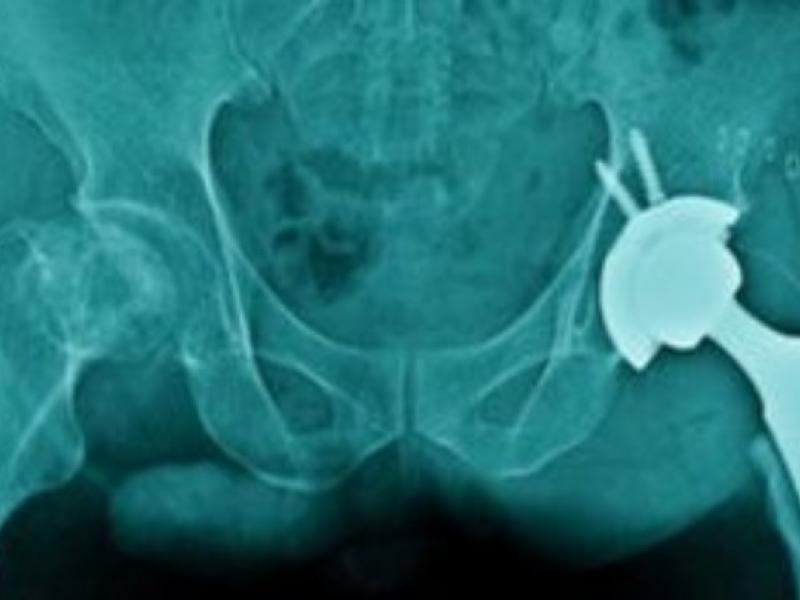

Το κάταγμα του ισχίου εξαιτίας οστεοπόρωσης, το οποίο είναι ήδη ένα επικίνδυνο πρόβλημα για τους ηλικιωμένους σε όλο τον κόσμο, εκτιμάται ότι θα γίνει ακόμη σοβαρότερο για τη δημόσια υγεία στο μέλλον, σύμφωνα με μια νέα επιστημονική έρευνα που εκτιμά ότι έως το 2050 τα περιστατικά σχεδόν θα διπλασιασθούν διεθνώς, εν μέρει λόγω της προϊούσας γήρανσης του παγκόσμιου πληθυσμού.

Η μελέτη κρούει τον κώδωνα του κινδύνου για την ανάγκη καλύτερης πρόληψης και θεραπείας, ιδίως για τους άνδρες και τους πολύ ηλικιωμένους άνω των 85 ετών που κινδυνεύουν περισσότερο. Η πιθανότητα ενός ατόμου να πάθει κάταγμα μετά τα 85 είναι υπερδιπλάσια σε σχέση με τις νεότερες ηλικιακές ομάδες.